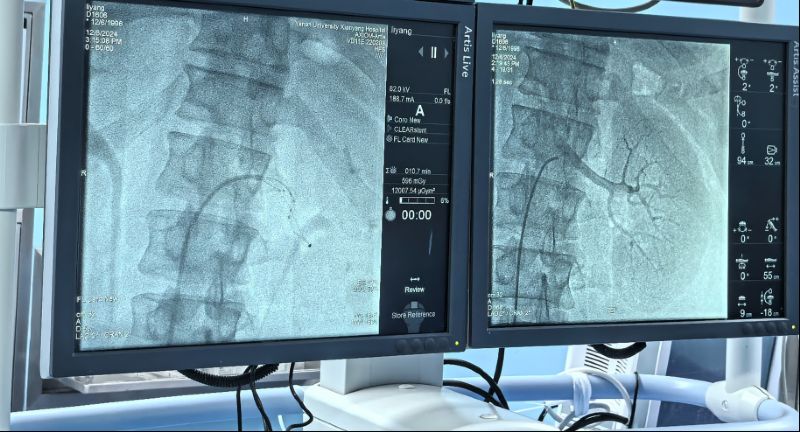

術(shù)中通過(guò)對(duì)左右腎動(dòng)脈造影,了解腎動(dòng)脈解剖結(jié)構(gòu)、評(píng)估腎臟灌注情況。而后順利將射頻消融導(dǎo)管的電極頭推至腎動(dòng)脈主干及分支中遠(yuǎn)段,雙側(cè)腎動(dòng)脈累計(jì)消融16次,涵蓋相應(yīng)分支及主干,共完成78個(gè)有效消融點(diǎn),完成后再次行雙腎動(dòng)脈造影,評(píng)價(jià)手術(shù)對(duì)腎動(dòng)脈形態(tài)和腎血流影響,累計(jì)用時(shí)僅60分鐘高效圓滿完成。術(shù)前血壓由154/110mmHg,手術(shù)完成后血壓130/94mmHg,即刻血壓下降效應(yīng)明顯,直至目前術(shù)后減少三種降壓藥物,監(jiān)測(cè)血壓維持在120/70mmHg左右,手術(shù)效果理想,長(zhǎng)期血壓下降情況我們將持續(xù)隨訪關(guān)注。